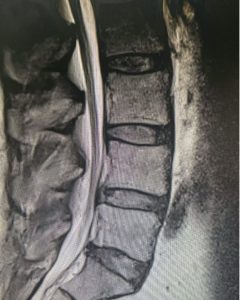

Here is a case that shows why spinal fusion is often needed along with laminectomy (decompression) surgery. It also illustrates the importance of having a thorough evaluation done by your doctor. What makes a thorough evaluation is having a complete history and proper X-rays.

Image 1: This patient had spinal stenosis at L4-5 on MRI that looks straightforward as the first image shows.